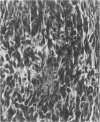

Charles River-CD Sprague-Dawley rats in 3 equal groups of 100 males and 100 females each were exposed to 12, 1, and 0 ppm of phenylglycidyl ether vapor for 24 months. Nasal tumors were first detected after 621 days' exposure at 12 ppm with an incidence of 11% in males and 4.4% in females. No nasal tumors were found at 1 ppm in rats exposed for 24 months. The nasal tumors, mostly epidermoid carcinomas, were derived from the respiratory epithelium and nasal glands, both of which revealed squamous metaplasia or dysplasia in the anterior nasal cavity. Most nasal tumors were confined to the anterior nasal cavity and occasionally invaded the dorsonasal bones and posterior nasal cavity. The undifferentiated glandular cells appear to differentiate to neoplastic squamous cells, because the ultrastructure of epidermoid carcinoma revealed traits of glandular cell differentiation in the neoplastic squamous cells. The features of glandular cell differentiation in the neoplastic squamous cells were intercellular or intracellular glandular lumens, secretory vesicles, mucus droplets, and intermediate cells showing both glandular and squamous differentiation. Squamous cells in the well-differentiated epidermoid carcinomas revealed abundant tonofibrils, desmosomes, glycogen particulates, and interdigitated cytoplasmic processes. These markers of squamous-cell differentiation were markedly reduced in the undifferentiated epidermoid carcinomas. The spindle-cell squamous carcinoma showed both squamous and fibroblastic-like differentiations. Some spindle cells had only fibroblastic-like differentiation, suggesting spindle-cell metaplasia of the squamous cells.